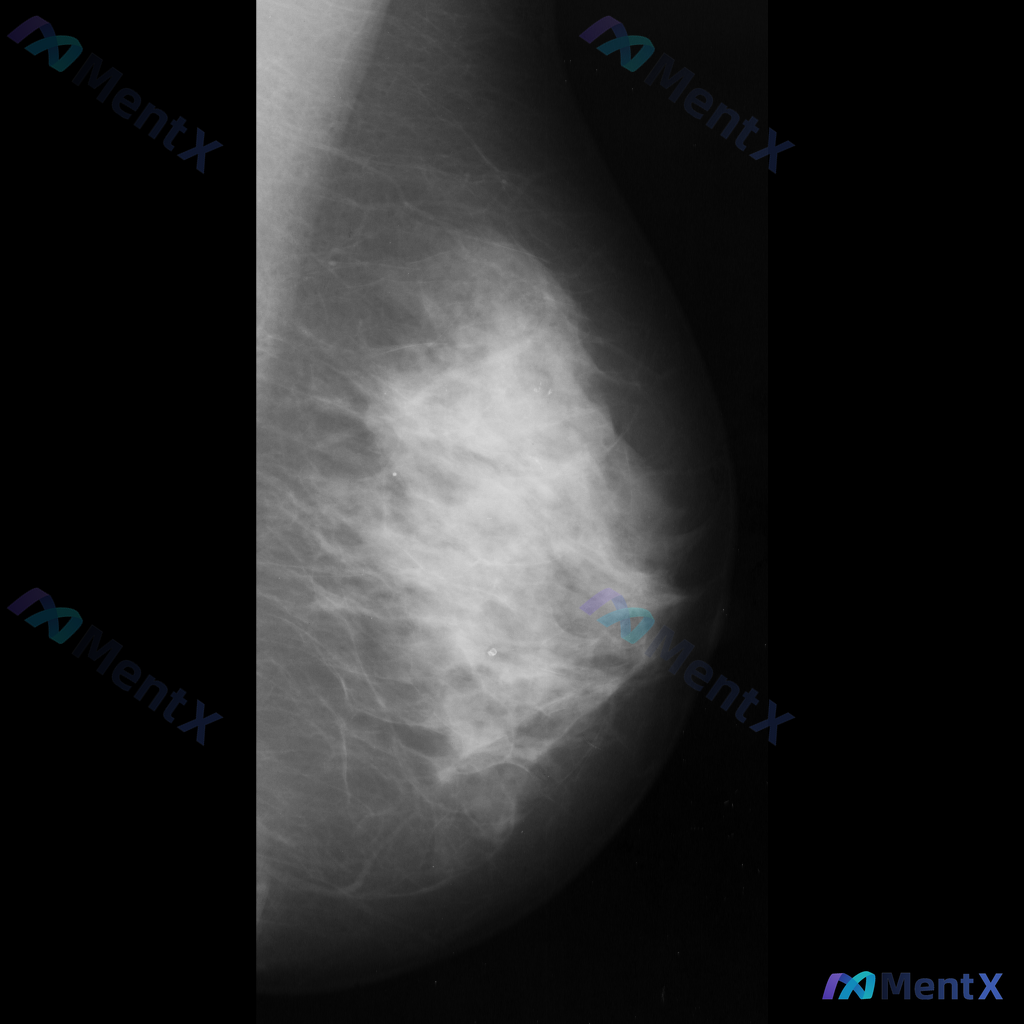

整理到一张乳腺钼靶影像资料,大家一起讨论下。 影像表现大概是这样: - 异常区域位于乳腺下象限偏外侧 - 可见一局限性致密影,形态大致呈卵圆形或不规则形 - 边缘部分清晰,局部可能模糊或有细微毛刺样改变 - 致密影密度高于周围脂肪组织,与纤维腺体组织密度相似或略高 - 周围乳腺小梁结构似有轻微的牵拉...

整理到一份单侧乳腺钼靶的影像资料,想和大家讨论一下读片思路: 影像背景与征象 - 背景:不均匀致密型乳腺 - 主要异常: 1. 乳腺中央及中下部可见一片边界模糊的斑片状/不规则形密度增高区 2. 该密度增高区域内,似乎存在乳腺正常小梁结构的牵拉或紊乱 3. 中下部偏乳头方向,有一组较为集中的、形态不...